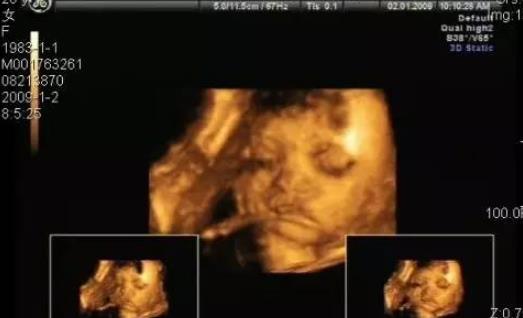

“三維B超很有意思的。我是從懷上小寶寶開始就決定給寶寶做三維彩超了,還詢問了醫生三維彩超什么時候做最好。做的那天看到寶寶高高的小鼻子,大大的小耳朵。因為是早上去的,小笨笨才睡醒,還看到他打哈欠,睜眼睛的樣子,超可愛的。還刻了盤,準備等孩子長大了給他看看自己還在媽媽肚子里是什么樣子。一輩子就這么一次,我覺得稍微貴點也是可以接受的!薄猼rinity

“還是要做一下。在通過多個途徑請教了不少權威彩超什么時候做最好之后,得出的結論是:26~30周時如果有條件,最好做一下彩超,因為這個時候看的最清楚,比如寶寶的小手小腳發育、心臟發育以及小嘴長得是否好等等。!薄K幕遮

“三維和四維B超的作用更多的是培養你和寶寶之間的親子感情,而不是篩查胎兒問題。B超醫師很可能會告訴你這類B超不是醫學檢查,不會關注胎兒是否有畸形。

做三維B超或四維B超最佳的時間是在懷孕26~30周之間。在孕26周之前,寶寶皮膚下的脂肪還非常少,所以臉部的骨骼會透過皮膚突顯出來。而孕30周以后,寶寶的頭可能會進入你的骨盆,這樣可能就看不到他的臉了。”——摘自孕期三維B超和四維B超

妊娠的24~32周為妊娠中期,此時期可清晰顯示胎兒各部位臟器,了解胎兒生長發育情況,觀察頭、肢體及各臟器大體結構是否有畸形。由于該期胎兒發育完善、羊水量增多,三維成像在液性環繞的條件下效果更佳,可顯示大部分組織器官結構及整個胎兒發育狀況,該期胎兒面部豐滿,五官清晰,是診斷的最佳時期,成像成功率高,對臨床診斷最有意義。